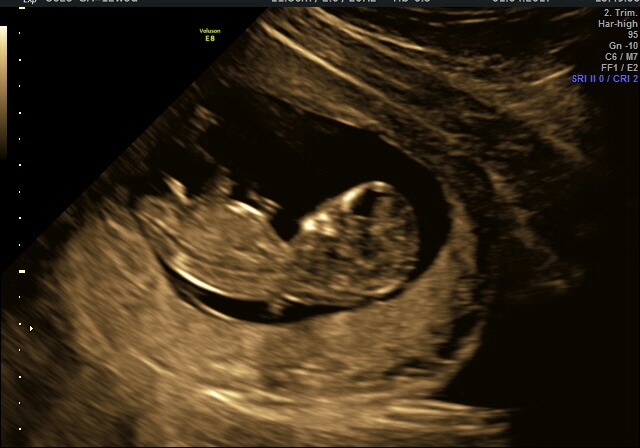

Хочу рассказать про скрининг у Батаевой Р. С. в мосплоде.

Сначала я сдала кровь, которая к моменту проведения УЗИ была уже готова и заключение она дала в итоге на руки и сразу общее.

🌼 КТР - 52, 5

🌼 ТВП - 1,5

🌼 ЧСС - 166

🌼 носовая - визуализируется

🌼 сердце для этого срока в норме, но надо в 16 недель идти для точности (я поэтому к ней и пошла)

🌼 ну и на 60% сказала пол, что очень порадовало папу - 👦))

🌼 кровь в норме - риск 1:2200

🌼 на сейчас все хорошо, чему я рада))

Стоимость - 9800, я не пожалела, потому что смотрела все маркеры, даже пятки мерили, сердце, вернее каналы, печень, почки и т.д.

+ дали диск, где 4 видео буквально в секундах и фото замеров основных.